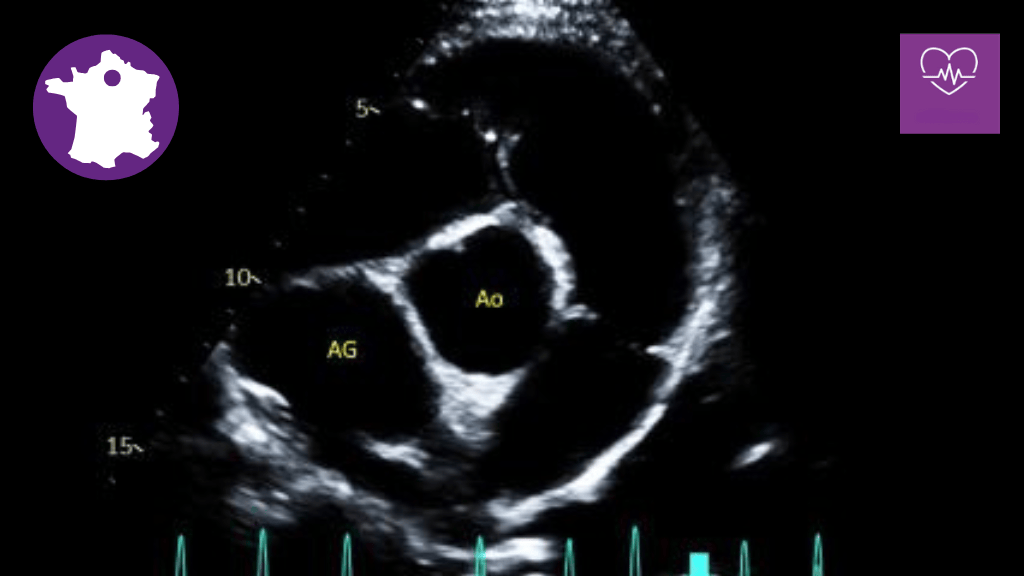

• Connaitre les coupes échocardiographiques les plus communes

• Apprendre les principes de l'écho-Doppler